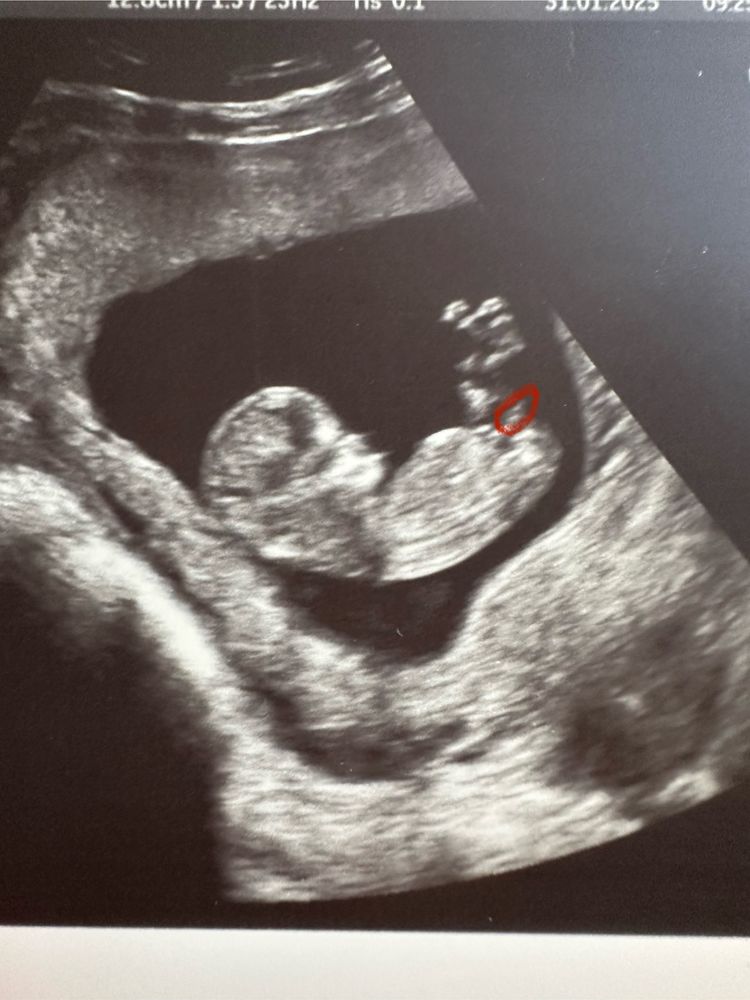

Мать добриков, а вот это разве не половой бугорок?) Изображение

31.01.2025